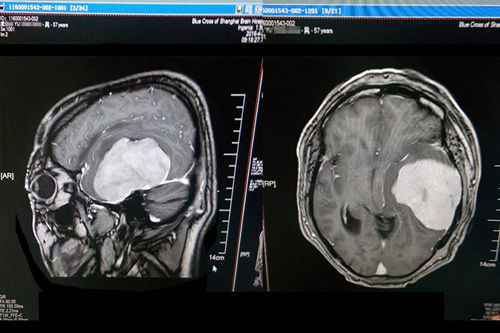

2016年4月,浙江宁波人,57岁的虞文军(化名)因巨大脑肿瘤(8*6cm) 前来上海蓝十字脑科医院就诊。经包括沈建康教授在内的专家会诊后,考虑到患者脑肿瘤巨大、肿瘤周边血供丰富,手术指征明确,常规手术切除恐出血过多,增加手术风险,决定术前先为虞文军行“超选择性全脑血管造影术+脑膜瘤供血动脉栓塞术”,对肿瘤供血动脉进行栓塞,减少出血量,再全麻下行“左侧颞底部巨大脑膜瘤切除术”。沈教授已经有十年未见过患者有如此大的肿瘤,患者术后随即恢复清醒,自我感觉头脑较前更清醒,语音、语速恢复较好,不到半个月便已能正常行走,顺利出院。

沈建康教授为虞文军成功施行巨大肿瘤切除术

术前磁共振影像显示巨大脑肿瘤